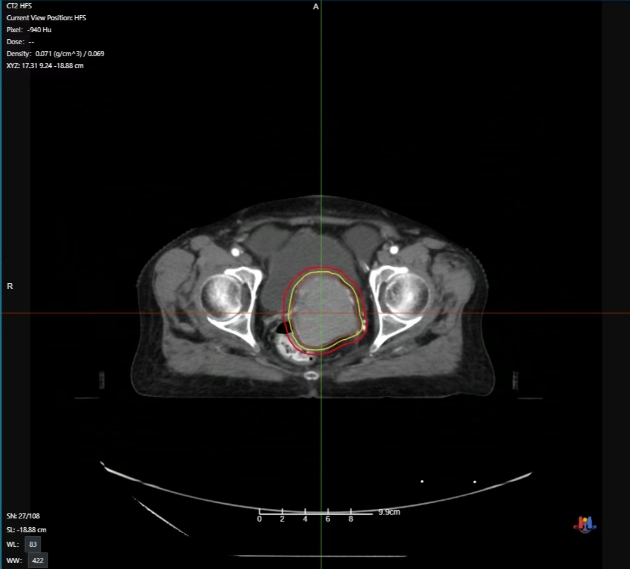

放疗初期病灶影像

肿瘤科医师综合考虑刘阿姨情况对其盆腔处病灶行姑息放射治疗,联影一体化CT直线加速器精准“狙击”肿瘤,高效率、高精度地杀灭肿瘤细胞,最大程度减轻放疗对周围正常组织的损伤。整个放疗周期中该患者病灶影像学上的变化情况如下。